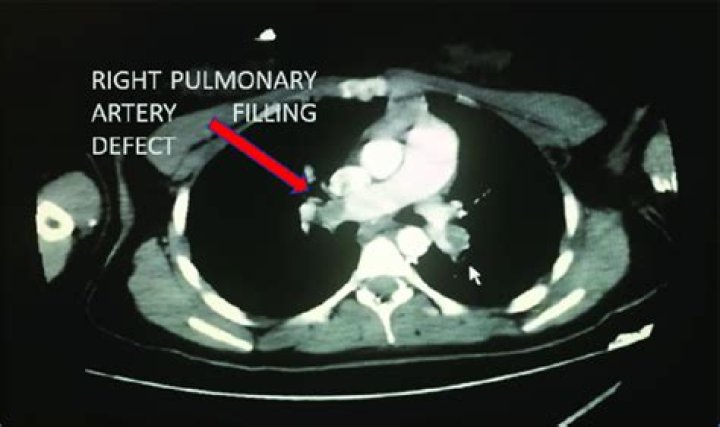

CONCLUSION: A filling defect in the pulmonary arterial stump seen on CT after pneumonectomy is thought to be an in situ thrombus caused by stasis of blood